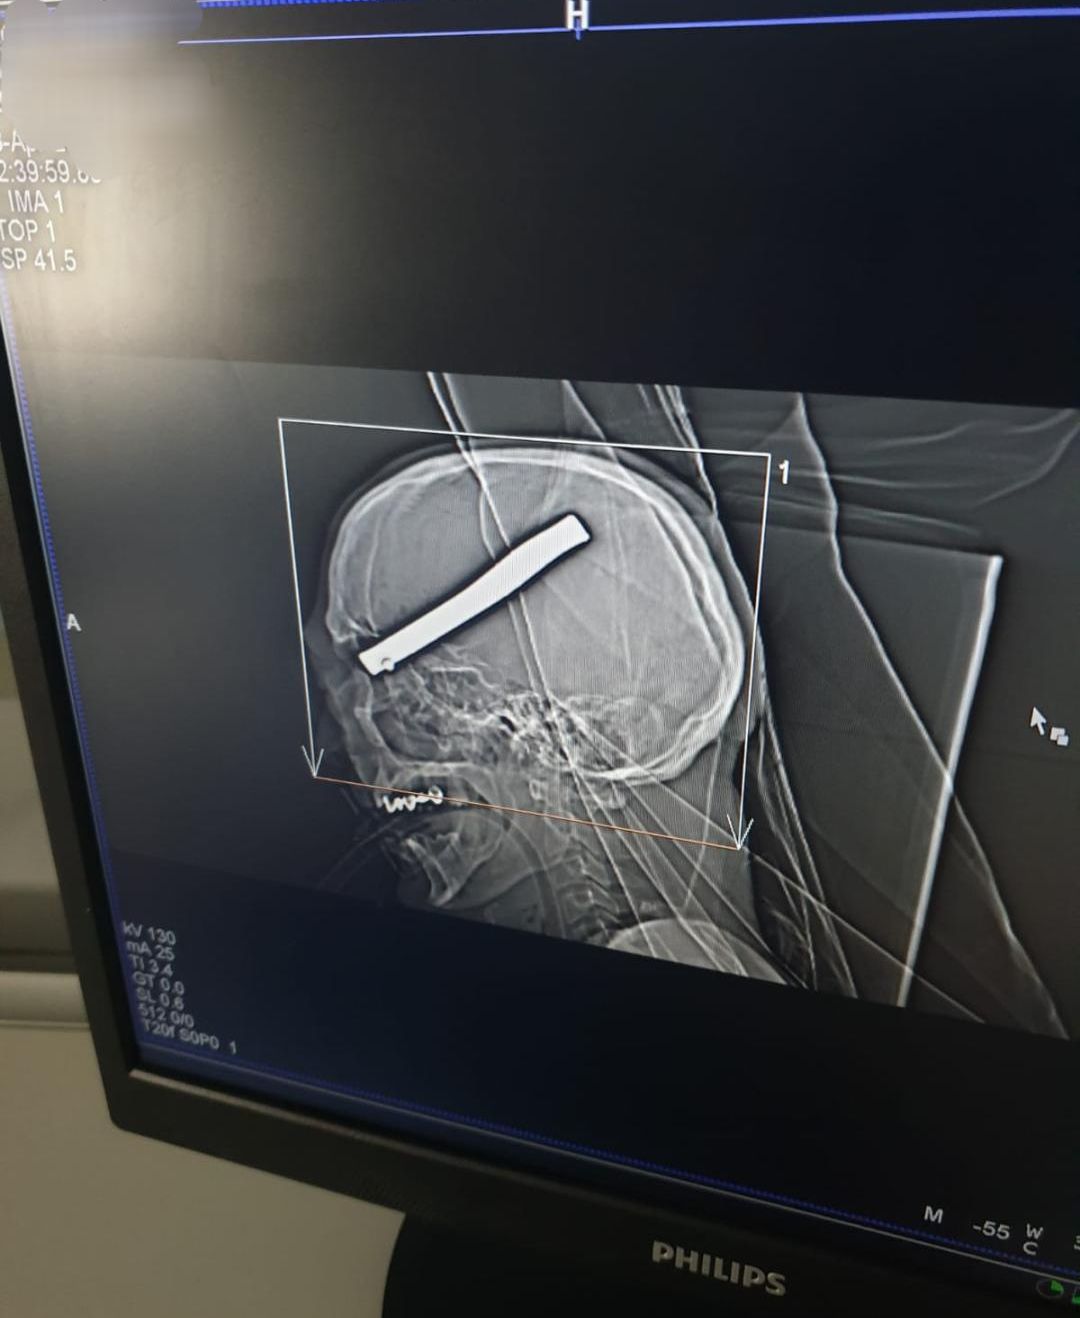

O tijă metalică de 20 de centimetri a rămas înfiptă în capul unui bărbat care repara o mașină

Accident de muncă cumplit aseară în garajul unui bărbat din comuna Hemeiuși. Vecinul său, în vârstă de 43 de ani, a fost grav rănit și doar o minune a făcut să fie încă în viață după ce o tijă metalică (foto) de aproximativ 20 de centimetri i-a pătruns în cutia craniană și a rămas în interior. Cei doi încercau să repare o mașină încă de ieri după amiaza, însă în jurul orei 21 vecinul a improvizat o cheie metalică, s-a aplecat peste motor și în momentul în care a forțat tija, aceasta a zburat și i s-a înfipt, prin ochi, în cutia craniană. Bărbatul a fost transportat de urgență la spital în stare de comă gradul IV, cu traumatism cranian sever și cu un corp străin la nivel cerebral. După o operație care a durat câteva ore, medicii neurochirurgi au reușit să îi extragă obiectul metalic din cutia craniană. Bărbatul este acum intubat mecanic la Secția de Terapie Intensivă a Spitalului Județean de Urgență Bacău.